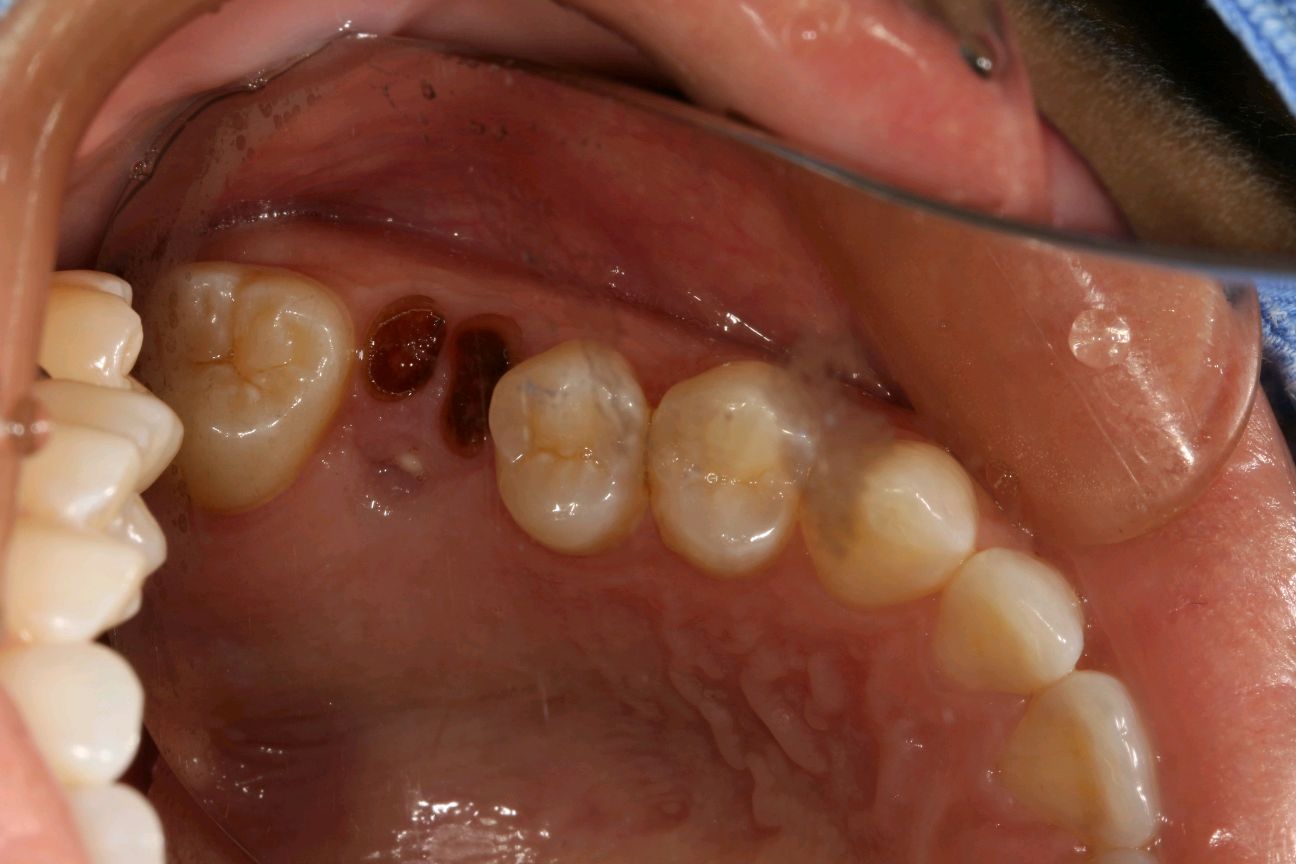

患者女,34岁,24、25邻面龋坏。经患者同意去腐备洞行嵌体修复。后通过德国 CEREC 技术扫描后,数据分析精准有效,"量身定做"专属于自己的修复体。患者当天即可配戴,既保证了边缘的密合性,还确保了色泽和形态的美观。患者不会有很强的异物感和咬合的不适。大大提高了工作的效率,也节省了患者的时间。

术前